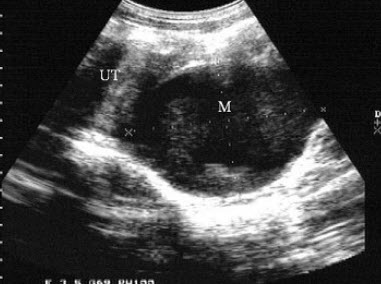

女性,18岁,月经不来潮就诊。超声检查如图,最可能的诊断为()

A.畸胎瘤

B.先天性无子宫

C.子宫肌瘤

D.双子宫

E.始基子宫